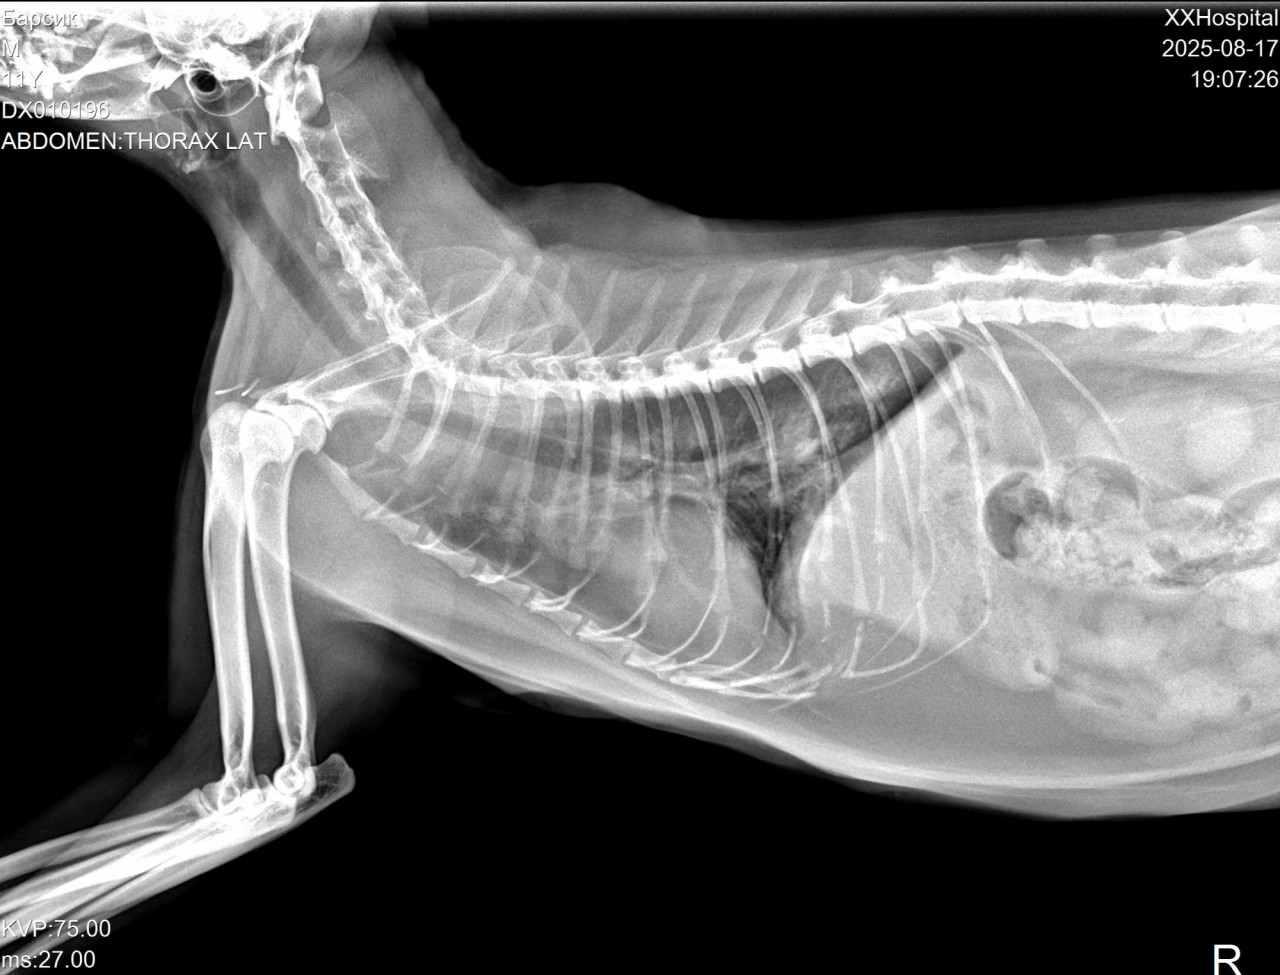

Кот стал хрипло мяукать. Ветеринар сказала сделать рентген грудной клетки. По снимкам сказала, что скорей всего новообразования, но не точно. Коту 12 лет.Также назначила кислород, и уколы ронколейкин, чтобы через неделю сделать повторно рентген. Велика ли вероятность, что это рак по снимкам?

Здравствуйте. По предоставленным рентген-снимкам грудной клетки у вашего кота действительно заметны изменения в области лёгких, которые могут соответствовать новообразованиям. Однако рентген не даёт 100% подтверждения диагноза «рак». Подобная картина может встречаться также при хронических воспалительных процессах (бронхит, пневмония), абсцессах или гранулёмах. Вероятность онкологии в 12-летнем возрасте повышена, особенно если изменения выглядят очаговыми или узловыми, но окончательно судить можно только после дополнительных исследований:

Здравствуйте. По рентген-снимкам у вашего кота действительно видны затемнения в грудной клетке, которые могут указывать на наличие новообразований. В то же время такие изменения иногда связаны с воспалительными процессами или скоплением жидкости поэтому только по рентгену окончательно сказать «рак» нельзя. В подобных случаях ветеринары ориентируются не только на снимки, но и на клинические проявления т.е на одышку, хриплое дыхание, кашель, общее состояние животного. Чтобы подтвердить или исключить опухоль, обычно рекомендуют дополнительные методы это повторный рентген, УЗИ грудной клетки, а при возможности и биопсию.

То, что вашему коту назначили кислород и поддерживающие препараты абсолютно оправдано так как это помогает стабилизировать его состояние и выиграть время до уточнения диагноза. Вероятность онкологии в таком возрасте выше среднего, но окончательное заключение можно дать только после комплексного обследования.